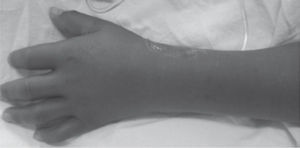

En la exploración de la piel se observó eCM generalizado, simétrico y bien delimitado. En el tronco se identificó en abdomen, espalda, cintura y región glútea, salpicado de múltiples M blanquecinas, redondas, confluentes de piel respetada y de diámetro variable, que en promedio midieron 1cm, dando el aspecto de “islas blancas en un mar rojo” (figs. 1 y 2). A nivel de miembros superiores, el ECM se observó más intenso en su región anterior y posterior de brazos y tercio distal de antebrazos; en donde se identificó el límite del exantema y piel sana, simulando una especie de “marca de nivel de agua”. En el dorso de ambas manos el exantema representó una tonalidad más rojiza acompañada de intenso edema que le confirió un aspecto de “piel más encendida” intensificada en la zona de venopunción (fig. 3). Se respetaron las palmas de las manos. Se corroboró el signo del torniquete y P en zonas de presión dorsal. A nivel de miembros inferiores, el eCM también mostró un carácter particularmente eritematoso intenso en la región anterior y posterior de ambas piernas, tercio distal de muslos, principalmente en rodillas; que a su vez se relacionó con LP puntiformes diseminadas (fig. 4). En la región dorsal de ambos pies el eritema fue menos intenso y se identificó un agrupamiento de LP y P1-3,34. Se respetó la región plantar. A la palpación, la paciente experimentó disestesias dolorosas y sensación de entumecimiento. La cara y tórax anterior fueron respetados. Entre los exámenes de laboratorio sobresalió que el recuento plaquetario fue disminuyendo progresivamente hasta llegar a 30,000. La radiografía de tórax no mostró alteraciones. El ultrasonido de hígado fue reportado como normal. Se descartó embarazo. La prueba inmunológica reportó DC. Se concluyó que la paciente fue portadora de la tríada del dengue, sin datos de alarma. Se inició manejo con hidratación, analgésicos y esteroides. Seis días después de su ingreso remitieron las MC. Se egresó por mejoría.